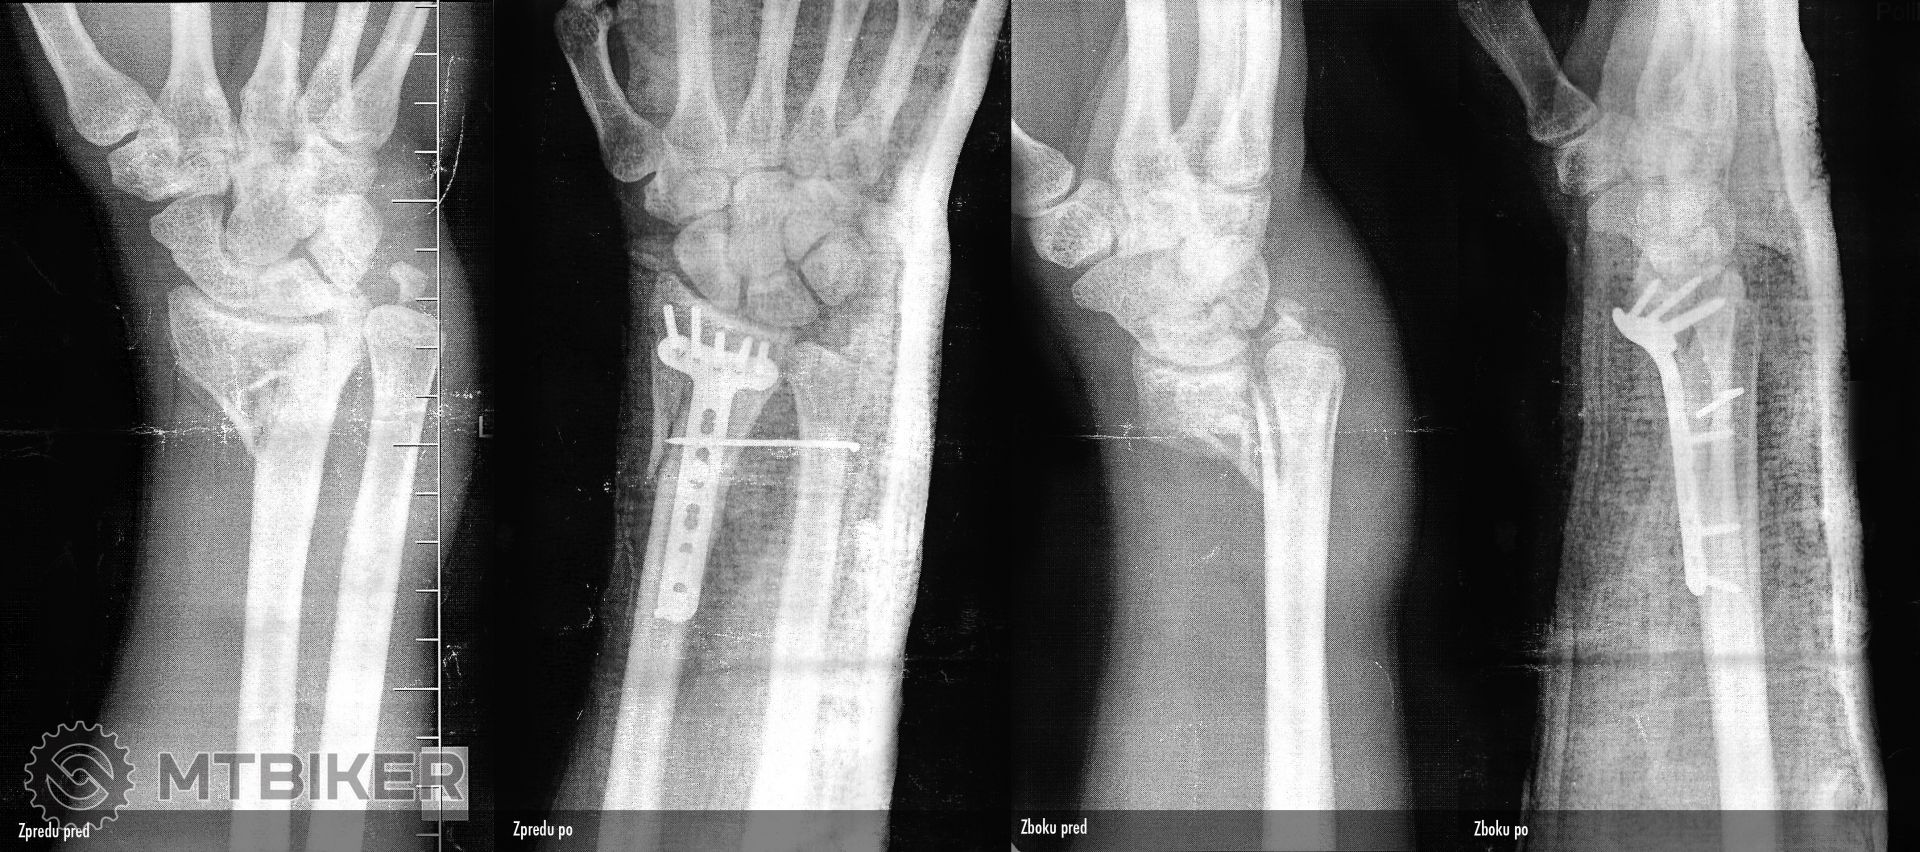

no veru pekny masaker zapastia, dobre si to tam mal rozhadzane...pekne pupratovali to mas teraz nejake cerstve ci uz davnejsie? rychlost asi bola celkom slusna ked to az tak rozhodilo tie kosti tak rychle a uspesne zahojenie...

No od padu je to uz dve sadry a jedna orteza, ktoru mi daju v pondelok dole. pred tyzdnom mi vybrali ten drot, ktory sa nejak zlomil, tak to bola velka zabava, platnicka a skrutky mi ostanu hadam zo 30-40 rokov

Rychlo som ale ani tak nesiel, ako som dopadol celou vahou v letku na ruku... malo ktora kost ostala na mieste, hned som videl ze to nieje v poriadku.

Klucna sa zlomila tiez, ale z toho nemam obrazok.